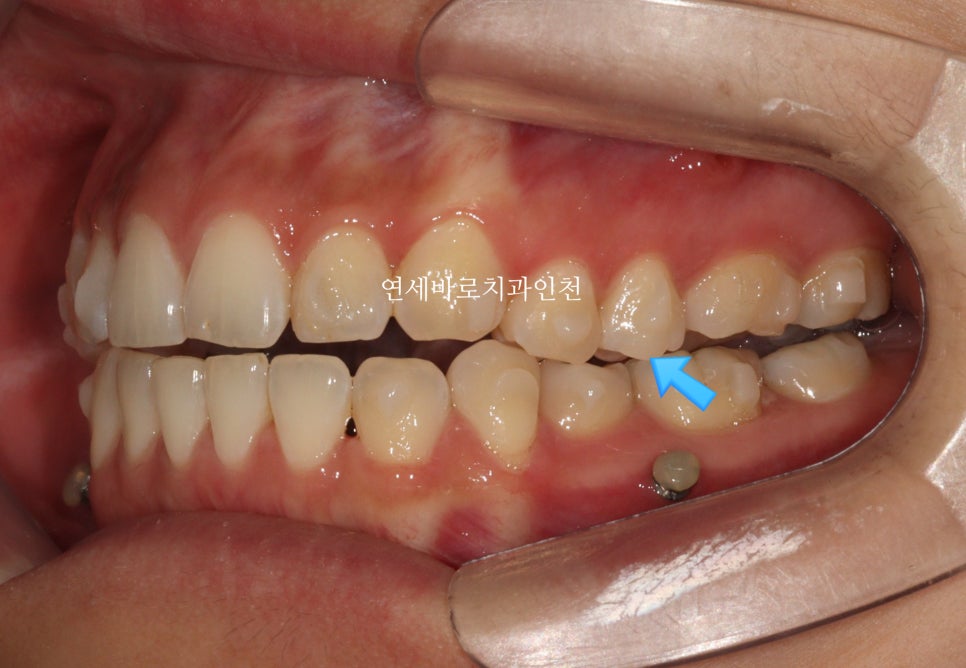

치료 초반의 모습입니다.

화살표 부분만 닿고 나머지는 다 닿지 않네요.

계획 그대로 진행되고 있는 겁니다.

무턱교정을 위해서는 위쪽 치아가 전체적으로 위쪽으로 올라가야합니다.

철사교정에서는 한덩어리로 잡고 한번에 올리지만

인비절라인에서는 다양한 옵션이 있는데, 이 환자분은 앞니, 그리고 어금니, 작은어금니를 나눠서 진행했습니다.

사진상 보이는 #미니스크류 도 사용하였습니다.

인비절라인 단독으로는 치료의 범위가 좁을 수 있지만, 미니스크류와 함께라면 조금 더 넓은 범위의 치료를 할 수 있습니다.